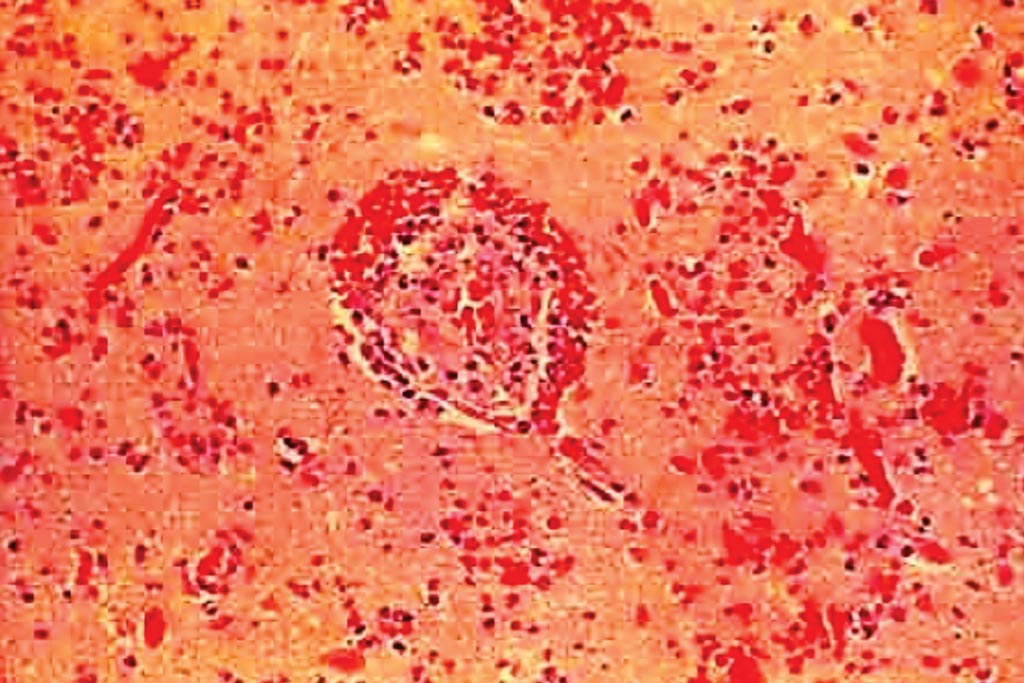

图片:一份脑出血性梗死的组织病理学,通常导致出现大量充满含铁血黄素的巨噬细胞(照片由美国National Institute of Neurological Disorders and Stroke提供)。